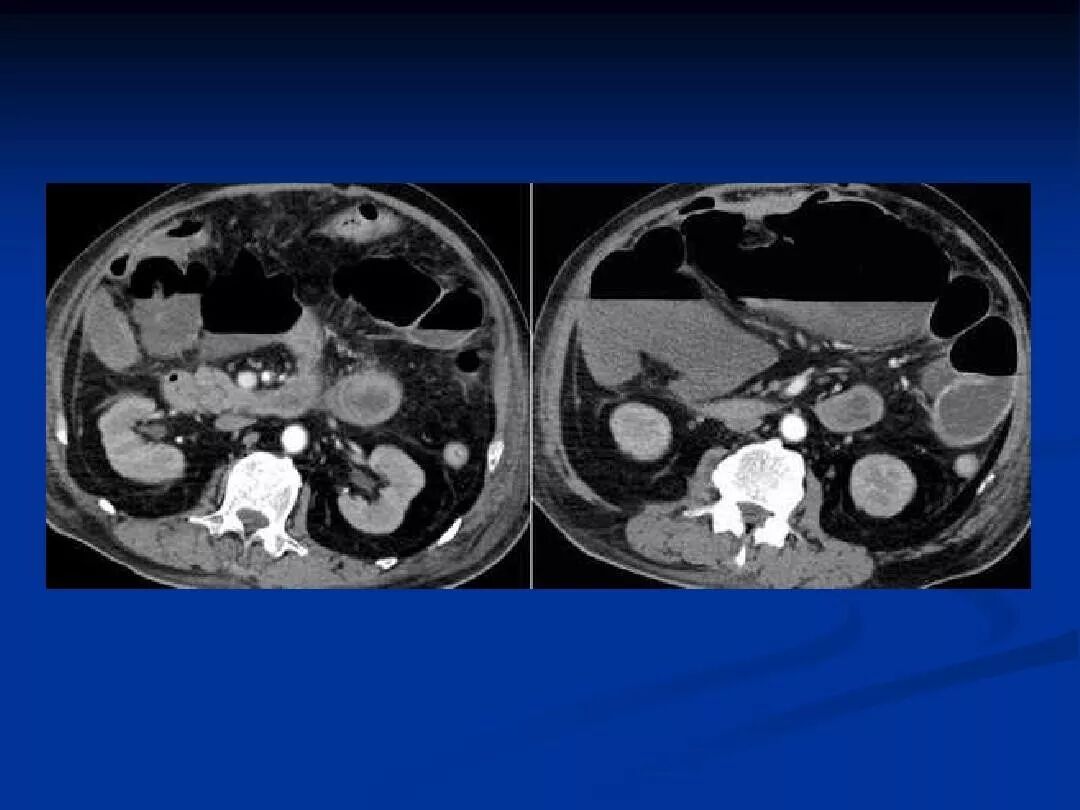

全腹部增强ct提示肠系膜上动脉栓塞.

肠系膜上动脉栓塞